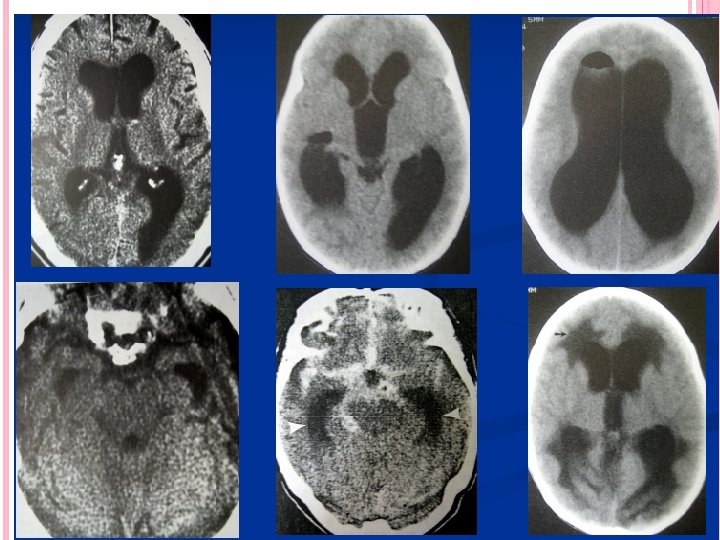

SÍNDROME DE DANDY WALKER Es una variedad de hidrocefalia congénita asociada a malformación de vermis cerebeloso y techo del cuarto ventrículo Imperforación de agujeros de Lushcka y Magendie LA MAYOR AFECCIÓN ES SOBRE EL 4 to. VENTRÍCULO, DILATADO FORMANDO BOLSA QUÍSTICA EN FOSA POSTERIOR HEMISFERIOS CEREBELOSOS APLANADOS Y RECHAZADOS HACIA LOS PEÑASCOS AGENESIA O DISFUNCIÓN DE CISTERNAS COMPROMISO EN LA CIRCULACIÓN Y REABSORCIÓN Villarejo Francisco. Martínez Lage Juan F. “NEUROCIRUGÍA PEDIÁTRICA”. Ediciones Ergón. Madrid España 2001

ANGIOGRAFÍA CEREBRAL Antes era fundamental el estudio del síndrome hidrocefálico, actualmente han quedado relegadas. Solo se utilizan para estudio de malformaciones vasculares que pudieran desencadenar hidrocefalia TOMOGRAFÍA CEREBRAL MÉTODO DE ELECCIÓN Tamaño de Cavidades ventriculares Causa Etiológica Villarejo Francisco. Martínez Lage Juan F. “NEUROCIRUGÍA PEDIÁTRICA”. Ediciones Ergón. Madrid España 2001 Neumoencefalografía Ventriculografía Cisternografía isotópica

Criterios para TAC Presencia de dilatación ventricular Hipodensidad en polos occipitales y frontales periventriculares Borramiento de los surcos cerebrales INDICE DE EVANS : igual o superior a 0. 30 debe considerarse patológico Cuernos temporales con diámetro mayor a 2 mm Lopez Ojeda Pablo, DIAGNOSTICO Y TRATAMIENTO DE LA HIDROCEFALIA CRONICA EN EL ADULTO, Barcelona hospital universitario 2009

Criterios para TAC FH/ID >0. 5 Abombamiento de los cuernos frontales y ventrículos laterales

RESONANCIA MAGNÉTICA HALLAZGOS EN RM Desproporción entre dilatación ventricular y surcos corticales Hipodensidades periventriculares 3 ventrículo redondeado Astas frontales contornos abombados Adelgazamiento y estiramiento del cuerpo calloso